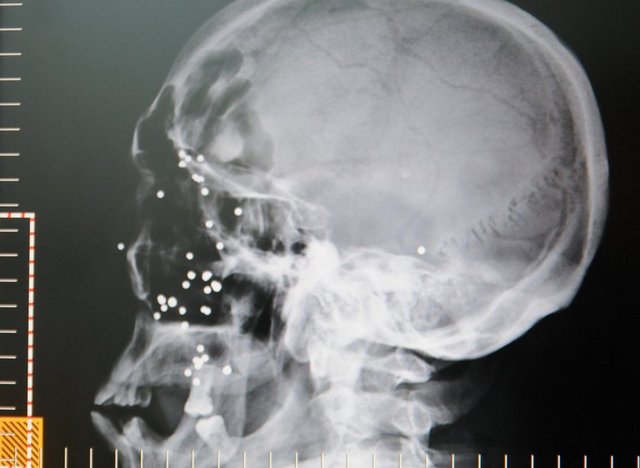

Çocukluğunda geçirdiği silah kazasında yüzüne isabet eden 38 saçmayla 54 yıldır birlikte yaşıyor.

1959 yılında meydana gelen olayda henüz 10 yaşında olan Hüseyin Akgemci, “dolma tüfek” olarak tabir edilen silaha bakım yaptığı esnada tüfeğin ateş alması sonucu yüzünden yaralandı. Sol yanağına isabet eden saçmalarla ağır yaralanan Akgemci, yakınları tarafından hastaneye kaldırıldı. Ameliyata alınan Akgemci 'nin yanağındaki saçmalardan bir kısmı alınsa da yeterli cerrahi müdahale imkanı olmadığı için 38 adet saçma Akgemci 'nin yüzünde kaldı. Hayatta kalan ve tek bir saçma dahi gözüne isabet etmeyen Akgemci, yanağındaki kurşunlarla yaşamını sürdürerek bugünlere geldi.

Akgemci 'nin filmlerini inceleyen Dr. Ali Kapukaya ise, saçmaların tek tek ayıklanamadığını söyledi. Kapukaya, “Hastamızın sol yanağında cilt altında çok sayıda saçma dediğimiz küçük ateşli silahtan çıkan metal cisimler mevcut. Ama bunlar cerrahi yolla tek tek ayıklanmıyor. Hastamız mecburen bu durumda kalacak” dedi.